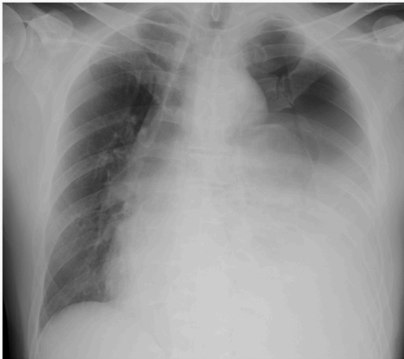

次日行胸腔穿刺术

,发现黑色胸腔积液(图2)。积液呈渗出性,淀粉酶水平升高(表1)。胸腔积液细胞学检查呈阴性。胸片显示左侧气胸和胸腔积液进展,纵膈向右移位(图3)。怀疑为张力性气胸,进行胸腔引流术,引流液中含有食物残渣和黑色胸腔积液,提示食管破裂。进行了鼻胃管插管,并抽取黑色胃液,与胸腔引流液相对应。胃镜检查

图3 次日胸片显示左侧气胸进展,纵隔向右侧移位